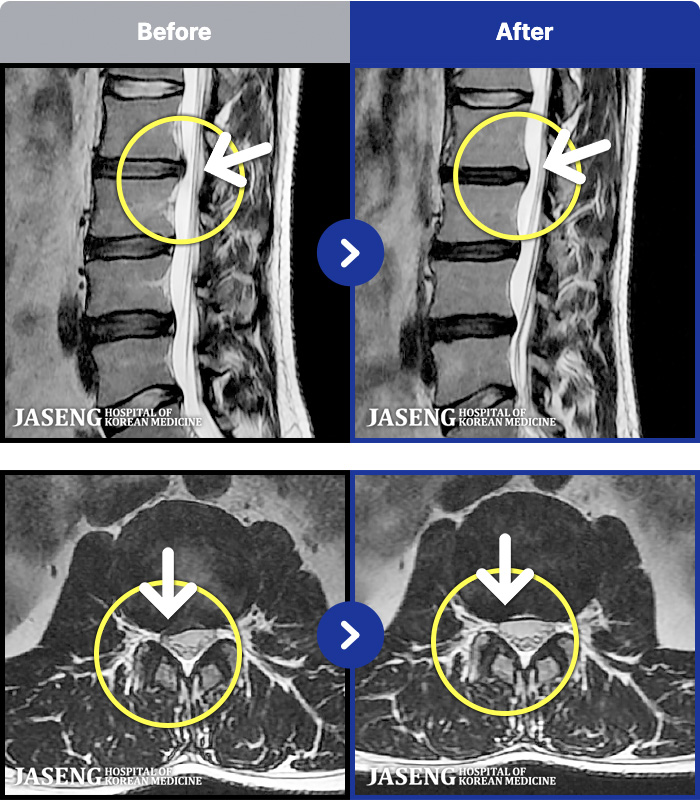

54 MRI ũ ʸ Ȯϼ.